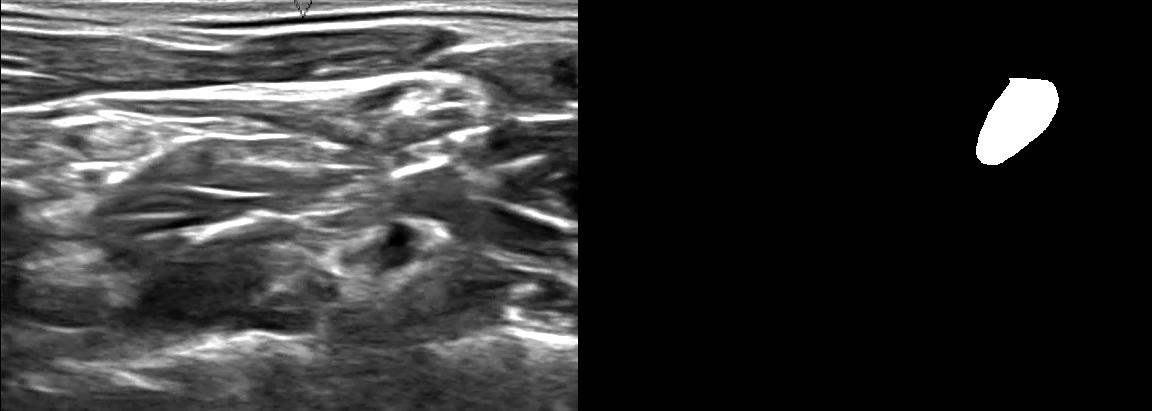

image

Слева — ультразвуковое изображение шеи, справа — нервная структура; на изображениях видно, что нахождение нервной структуры является нетривиальной задачей даже для человека (не являющимся специалистом в этой области)

Точное нахождение нервной структуры на ультразвуковых изображениях является важных этапом в эффективной вставке катетера для блокирования или уменьшения боли. Такие катетеры, в частности, помогают пациентам с наркотической зависимостью быстрее восстанавливаться.

Наилучший результат по мере сходства Дайса DSC на kaggle составил — 0.73226.